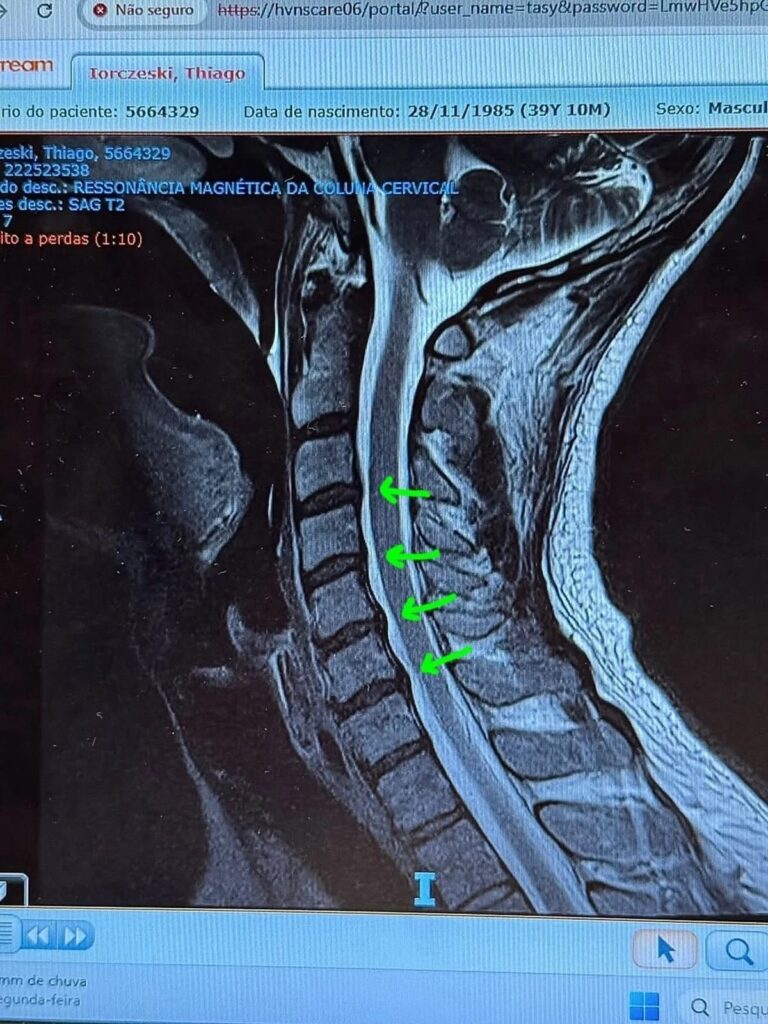

O cantor lindíssimo apareceu internado neste domingo e contou que está enfrentando uma crise de hérnia de disco na cervical.

Ele explicou o drama da hérnia com um textão didático. Falou que entre as vértebras existem discos que funcionam como amortecedores e que quando isso dá ruim acontece o tal herniamento.

Tiago já tinha passado por um episódio parecido há uns quatro anos. Na época sugeriram cirurgia, mas ele escapou na base da osteopatia, pilates e muita fé. Só que agora as coisas pioraram e os médicos decidiram fazer um bloqueio inflamatório com injeções direto na coluna. Ele ainda pediu boas energias.